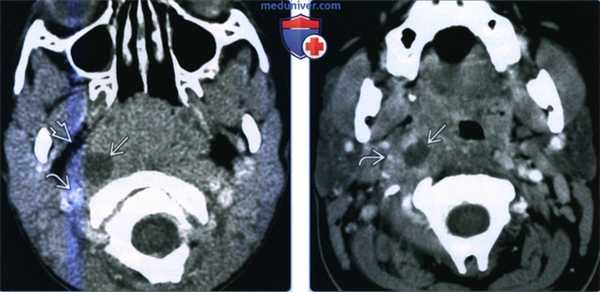

(Слева) При КТ с КУ в аксиальной проекции определяется большой МА с содержимым пониженной плотности. Распространения в окологлоточное пространство за пределы капсулы миндалины нет. Левая миндалина увеличена и накапливает контраст, но признаков абсцедирования нет. Обратите внимание на сопутствующий выпот в заглоточном пространстве.

(Справа) При КТ с КУ в аксиальной проекции определяются миндаликовые абсцессы с обеих сторон, левый по размерам больше правого. Абсцессы сдавливают оба окологлоточных пространства, но распространения воспалительного процесса на окружающие структуры нет. Просвет дыхательных путей сужен и имеет щелевидную форму.

• КТ с КУ:

о Миндаликовый абсцесс: увеличенная небная миндалина(ы) с центральным участком пониженной плотности и периферическим кольцом накопления контраста:

- По данным КТ с контрастированием дифференцировать отек миндалины от сформированного абсцесса сложно

- Очень важно дифференцировать МА от простого воспаления миндалины, поскольку лечение может различаться

- Воспалительная исчерченность окружающих клетчаточных пространств

о Паратонзиллярый абсцесс: миндаликовый абсцесс распространяется в окружающие пространства:

- Окологлоточное, жевательное, поднижнечелюстное пространства

о У подростков и у взрослых часто сочетается с выраженной двусторонней реактивной шейной аденопатией